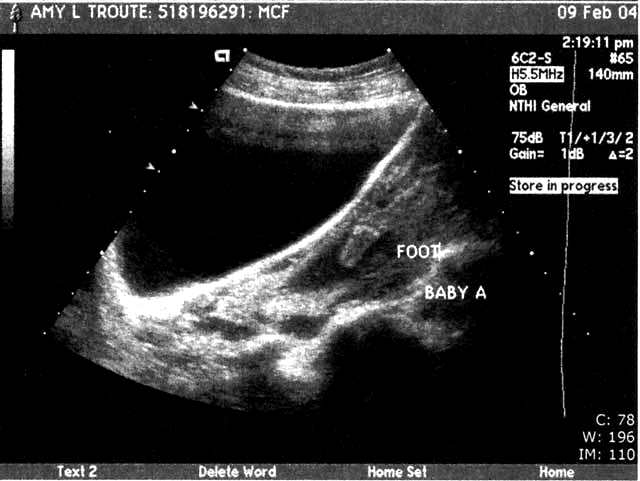

| We had our BIG ultrasound on February 9. Here are a few of the 111 pictures that were taken (everything from areas of the brain to little tiny kidneys) in our nearly 2-hour appointment (click the pictures to get a larger view – note the one where Baby A’s foot is right above Baby B’s head – so cute!!). The babies were moving so much that the tech had to literally hold them down with the ultrasound wand to get the detailed pictures she needed! Talk about uncomfortable!! Whew!! We were thrilled to hear that they’re developing perfectly – measuring in at 14cm and 9oz each!! They even bumped my due date up a week since the babies were measuring bigger than normal – music to our ears!! We’re still shooting for late June… I’d be at 36 weeks on my birthday – I’d love to share June 17 with the twins…or our anniversary June 23, or Father’s Day… ;o) We heard the heartbeats at a doctor’s appointment on 2/18 and my “theory” of their different heart rates signaling “boy and girl” was blown… In each of our past appointments there was a 10-15 beat difference between the two, but this time both were right at 160 beats per minute. I guess Reese is right – I really have no idea who’s in there! This week (2-16 to 2-20) I’ve started to really feel the babies moving! They’re especially active from 2-5 in the afternoon… makes it so hard to concentrate! I love it! I can't imagine how it's going to feel once they weigh more than 9 or 10oz each... Two 4 or 5lb kiddos in there packing on the pounds, rolling around and sticking their feet in each other's faces... Hahaha! What an image!! And the thought of them being most active at night... The adventure is only beginning!" |